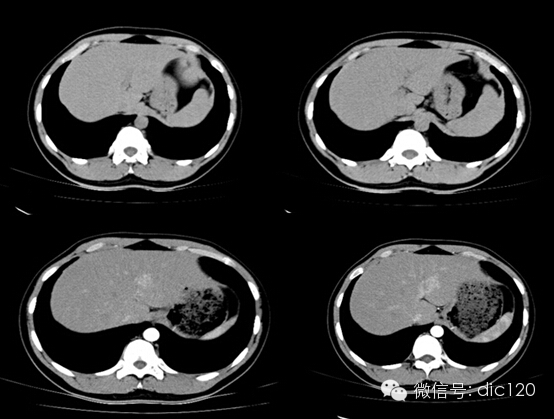

男,21Y,門診患者,病史不詳影像表現:CT平掃與正常肝組織呈等密度,密度均勻,動脈期病灶快速明顯均勻強化,中心見小片狀低密度影(瘢痕),門脈期及延遲期對比劑快速退出呈等密度,中央低密度影延遲強化。MRI腫塊T2WI為稍高信號,中央高信號。動態增強掃描動脈期均顯著增強,門脈期輕度增強,延遲期瘢痕強化。

隨訪外院手術病理:肝FNH。

鑒別診斷:1、肝血管瘤:增